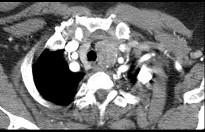

问题 40岁,女,发现颈部肿块,随吞咽上下移动,触之无搏动,咳嗽、气喘1周,请结合CT,检查选择最可能的诊断 ( )

选项 A.胸腺瘤 B.胸内甲状腺瘤 C.无名动脉瘤 D.无名动脉伸展扭曲 E.淋巴瘤

答案 B